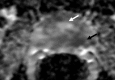

Materials and methods: In this institutional review board-approved (with waiver of informed consent), HIPAA-compliant study, 38 foci of carcinoma, 38 SH nodules, and 38 GH nodules in the CG were analyzed in 49 patients (26 with CG carcinoma) who underwent preoperative endorectal magnetic resonance (MR) imaging and radical prostatectomy. All carcinomas and hyperplastic foci on MR images were localized on the basis of histopathologic correlation. The apparent diffusion coefficient (ADC), the contrast agent transfer rate between blood and tissue (K(trans)), and extravascular extracellular fractional volume values for all carcinoma, SH, and GH foci were calculated. The mean, standard deviation, 95% confidence interval (CI), and range of each parameter were calculated. Receiver operating characteristic (ROC) and multivariate logistic regression analyses were performed for differentiation of CG cancer from SH and GH foci.

Results: The average ADCs (× 10(-3) mm(2)/sec) were 1.05 (95% CI: 0.97, 1.11), 1.27 (95% CI: 1.20, 1.33), and 1.73 (95% CI: 1.64, 1.83), respectively, in CG carcinoma, SH foci, and GH foci and differed significantly, yielding areas under the ROC curve (AUCs) of 0.99 and 0.78, respectively, for differentiation of carcinoma from GH and SH. Perfusion parameters were similar in CG carcinomas and SH foci, with K(trans) yielding the greatest AUCs (0.75 and 0.58, respectively). Adding K(trans) to ADC in ROC analysis to differentiate CG carcinoma from SH increased sensitivity from 38% to 57% at 90% specificity without noticeably increasing the AUC (0.79).

Conclusion: ADCs differ significantly between CG carcinoma, SH, and GH, and the use of them can improve the differentiation of CG cancer from SH and GH. Combining K(trans) with ADC can potentially improve the detection of CG cancer.